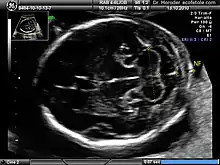

Correct modified axial plane for the measurement of the nuchal fold in the second trimester[17].

Nuchal translucency testing is distinctly different from and should not be confused with nuchal thickness testing. At the end of the first trimester (14 weeks), the nuchal translucency can no longer be seen and instead the nuchal fold thickness is measured between 16 and 24 weeks gestation. The fold is more focal and at the level of the posterior fossa. This measurement has a higher threshold of normal, although the implications of increased thickness are similar to those of translucency. The nuchal fold thickness is considered normal if under 5mm between 16 and 18 weeks gestation and under 6mm between 18 and 24 weeks gestation. An increased thickness corresponds to increased risk for aneuploidy and other fetal abnormalities.